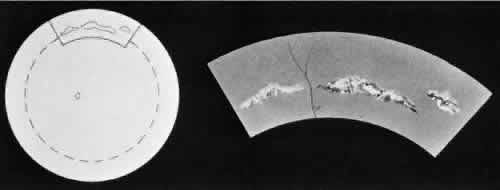

degeneration (Fig. 8).  Fig. 8. Meridional fold in a young patient. Retina is thickened along course of

fold, which shows microcystoid change near the surface and a cap of dense-staining

glial cells along its surface. Middle and outer layers of

the retina are largely unremarkable. Pigment epithelium shows focal

redundancy anteriorly. (Hematoxylin-eosin; × 150.) Fig. 8. Meridional fold in a young patient. Retina is thickened along course of

fold, which shows microcystoid change near the surface and a cap of dense-staining

glial cells along its surface. Middle and outer layers of

the retina are largely unremarkable. Pigment epithelium shows focal

redundancy anteriorly. (Hematoxylin-eosin; × 150.)